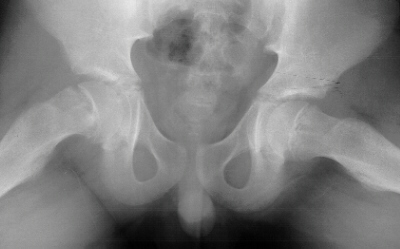

An AP pelvis and frog-leg lateral radiographs of both hips were obtained.

On the AP pelvis radiograph, there was notable widening and irregularity

of the proximal femoral epiphyseal growth plate, and Klein's line did not

intersect the epiphysis

.

The frog-leg lateral view of the right hip demonstrated an obvious grade

1 slipped capital femoral epiphysis